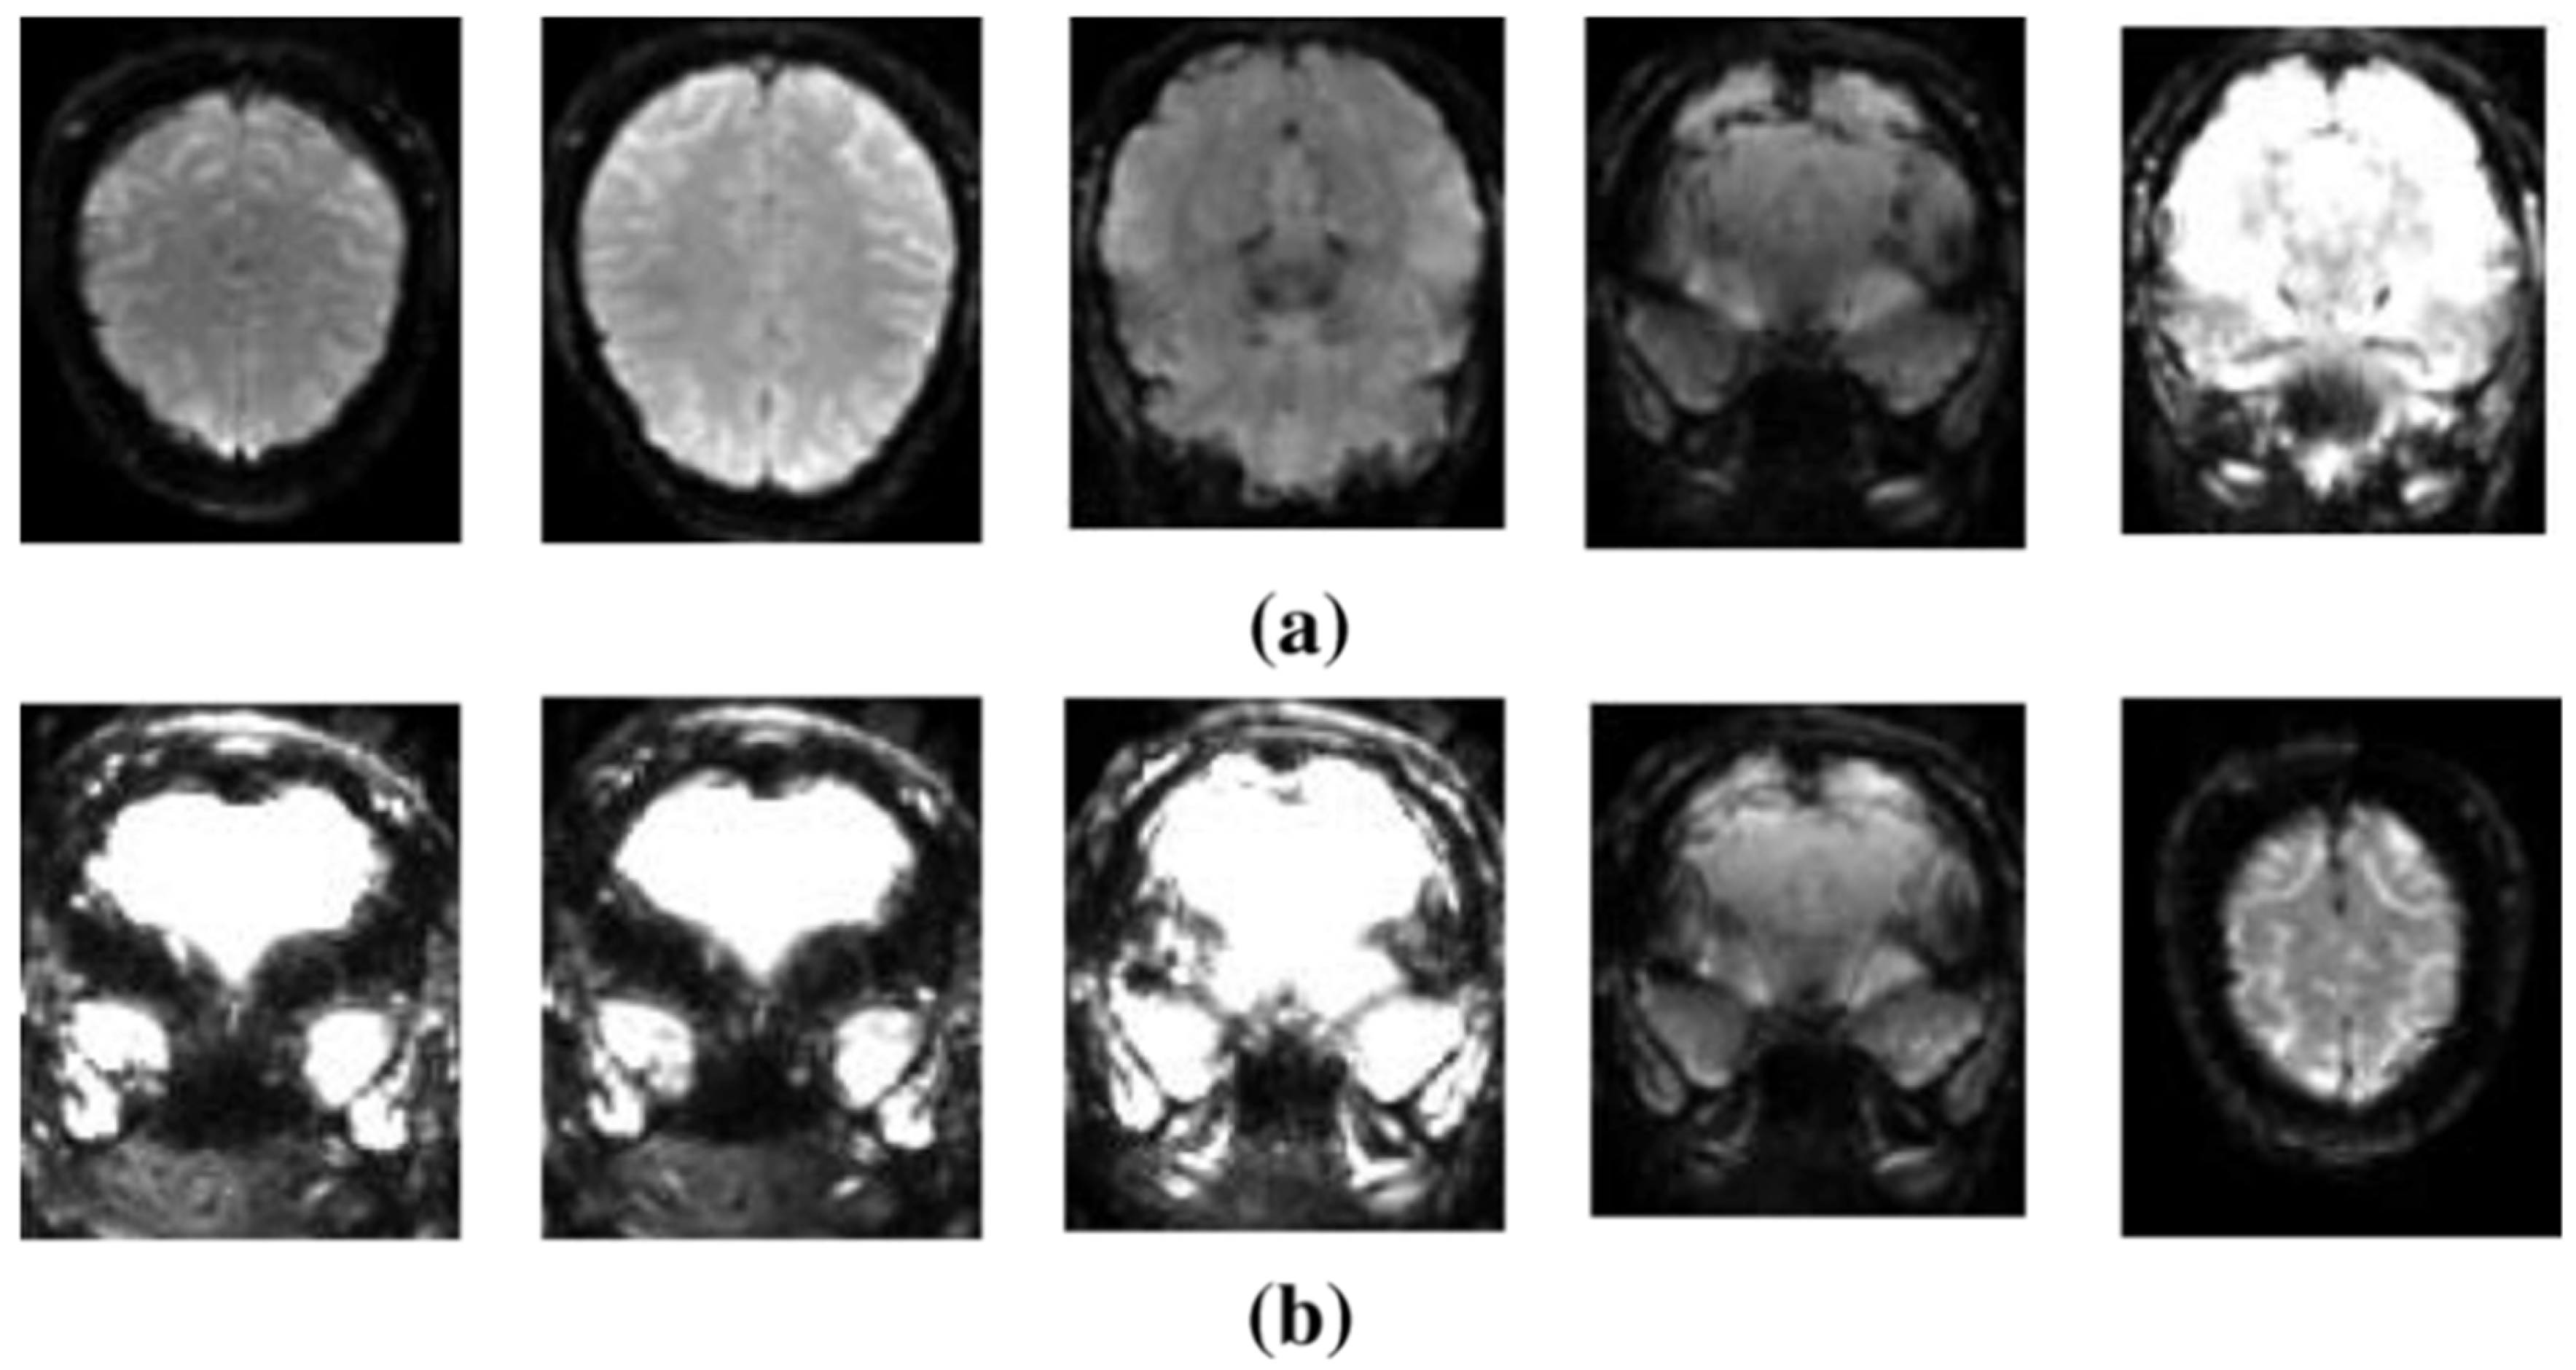

4.3. fMRI-Based Diagnosis of SZ

- fMRI has high spatial resolution, allowing researchers to identify the location of brain activity. On the other hand, its temporal precision being restricted, it measures fluctuations in the activity of the brain over seconds instead of milliseconds. Improving the temporal resolution of fMRI and better combining it with EEG can provide a more thorough picture of brain function.

- There is ongoing disagreement concerning whether task-based or resting-state fMRI is more effective in diagnosing SZ. Task-based fMRI requires participants to execute specific tasks, whereas resting-state fMRI monitors brain activity at rest. Each methodology has merits and demerits; hence, additional studies are required in order to establish the most efficient method for detecting SZ.

- fMRI data are complicated and multidimensional, necessitating modern computer approaches for analysis. Meaningful patterns can be extracted from fMRI data using methods such as ML and network analysis. However, more robust and interpretable models are needed to provide unambiguous insights into brain activity in SZ.